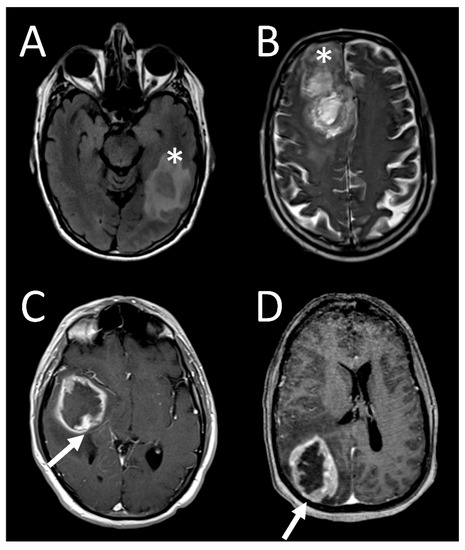

MGMT methylated tumors were less likely to demonstrate ependymal extension than MGMT unmethylated tumors in the control group (Figure 2), reaching statistical significance (p = 0.01, Fisher’s exact test). No MGMT methylation-dependent difference in the rate of ependymal extension was seen in the 19/20 co-gain group (Table 5). None of the other VASARI features demonstrated significant MGMT methylation-dependent difference (Table S1).

Figure 2.

Sample imaging features of glioblastoma without 19/20 co-gain. FLAIR image of MGMT methylated tumor located in the left temporal lobe (A, asterisk). T2 images of MGMT unmethylated tumor located in the right frontal lobe (B, asterisk). T1 postcontrast image of MGMT unmethylated tumor located in the right temporal lobe demonstrating ependymal extension (C, arrow). T1 postcontrast image of MGMT unmethylated tumor located in the right parietal lobe demonstrating pial invasion posteriorly (D, arrow).